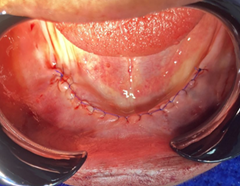

Luego de culminar la regularización, pasamos a suturar la incisión, esto para unir los tejidos blandos y permitir una correcta recuperación del paciente con la aplicación de técnicas de sutura e hilos, con este procedimiento tenemos varios objetivos entre ellos la alineación y estabilidad de los tejidos, para una homeostasia ya que la sutura ejerce presión sobre los vasos sanguíneos dañados lo que ayuda a la formación de coágulos y disminuye el riesgo de complicaciones hemorrágicas, da protección a la herida generando una barrera física que evita la contaminación bacteriana y por su puesto promueve una correcta cicatrización. En el caso de nuestra paciente utilizamos la técnica de sutura continúa reforzada con el hilo de nylon #4.0. (Figura 6)

Figura 6. Proceso de sutura.

Elaboración: Los autores.